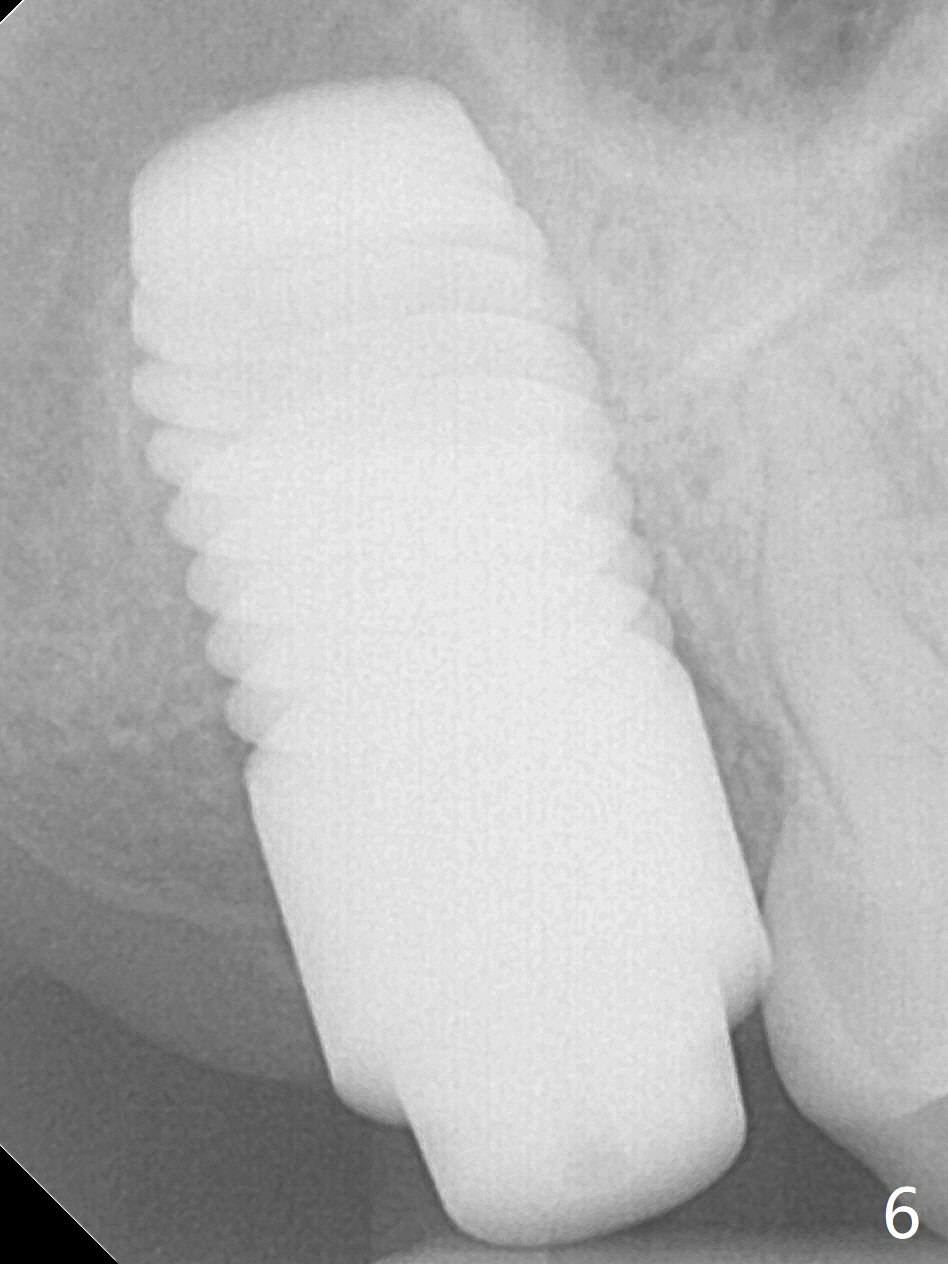

Preop exam shows that the tooth #2 has split into the buccal (Fig.1 B) and palatal (P) halves. When the tooth is extracted (Fig.2), there is a large piece of granulation tissue between these halves. The socket is large with sinus floor having pointed perforation. The latter is enlarged with rounded tapered Tatum osteotomy 2-4 mm, followed by tapered and then rounded taps. A 6.8x14 mm rounded tap has barely enough stability (Fig.3). Following placement of 2 PRF plug and 2 PRF membranes and allograft/Osteogen, a 8x17 mm cylindrical implant is placed with 60 Ncm (implant machine reading), however the implant is unstable (Fig.4). More graft is placed around the implant. With placement of 6x3 mm abutment, an immediate provisional is fabricated to close the socket. There is nasal discharge for a few days postop. PAs taken nearly 6 months postop show no bone loss (Fig.5,6). The definitive crown is cemented with access hole; there is no residual cement (Fig.7 (9 months postop)). The crown is loose 1 month post cementation (last March, Fig.8 with periimplant space (*)). The unipost was not cemented due to gag reflex. He refuses treatment immediately because of the allergy season. When he returns, spray a topical to his throat. Following crown removal, implant is found to have mobility. Panoramic X-ray (Fig.9) and CT (Fig.10,11) show fibrointegration (space) and implant intrusion into the sinus (S) without bone formation. After implant removal, the sinus floor and membrane are found to have been perforated. Osteogen plug is placed, followed by Vanilla/Osteogen (Fig.12 *) and Osteogen plug. It appears that an immediate implant is contraindicated when there is severe infection (Fig.2) with sinus floor perforation. In this case, the bone density at the upper 2nd molar is low (Fig.10 distopalatal view of 3-D image). Bone expansion and condensation is needed for implantation. Progressive loading is also necessity prior to impression.